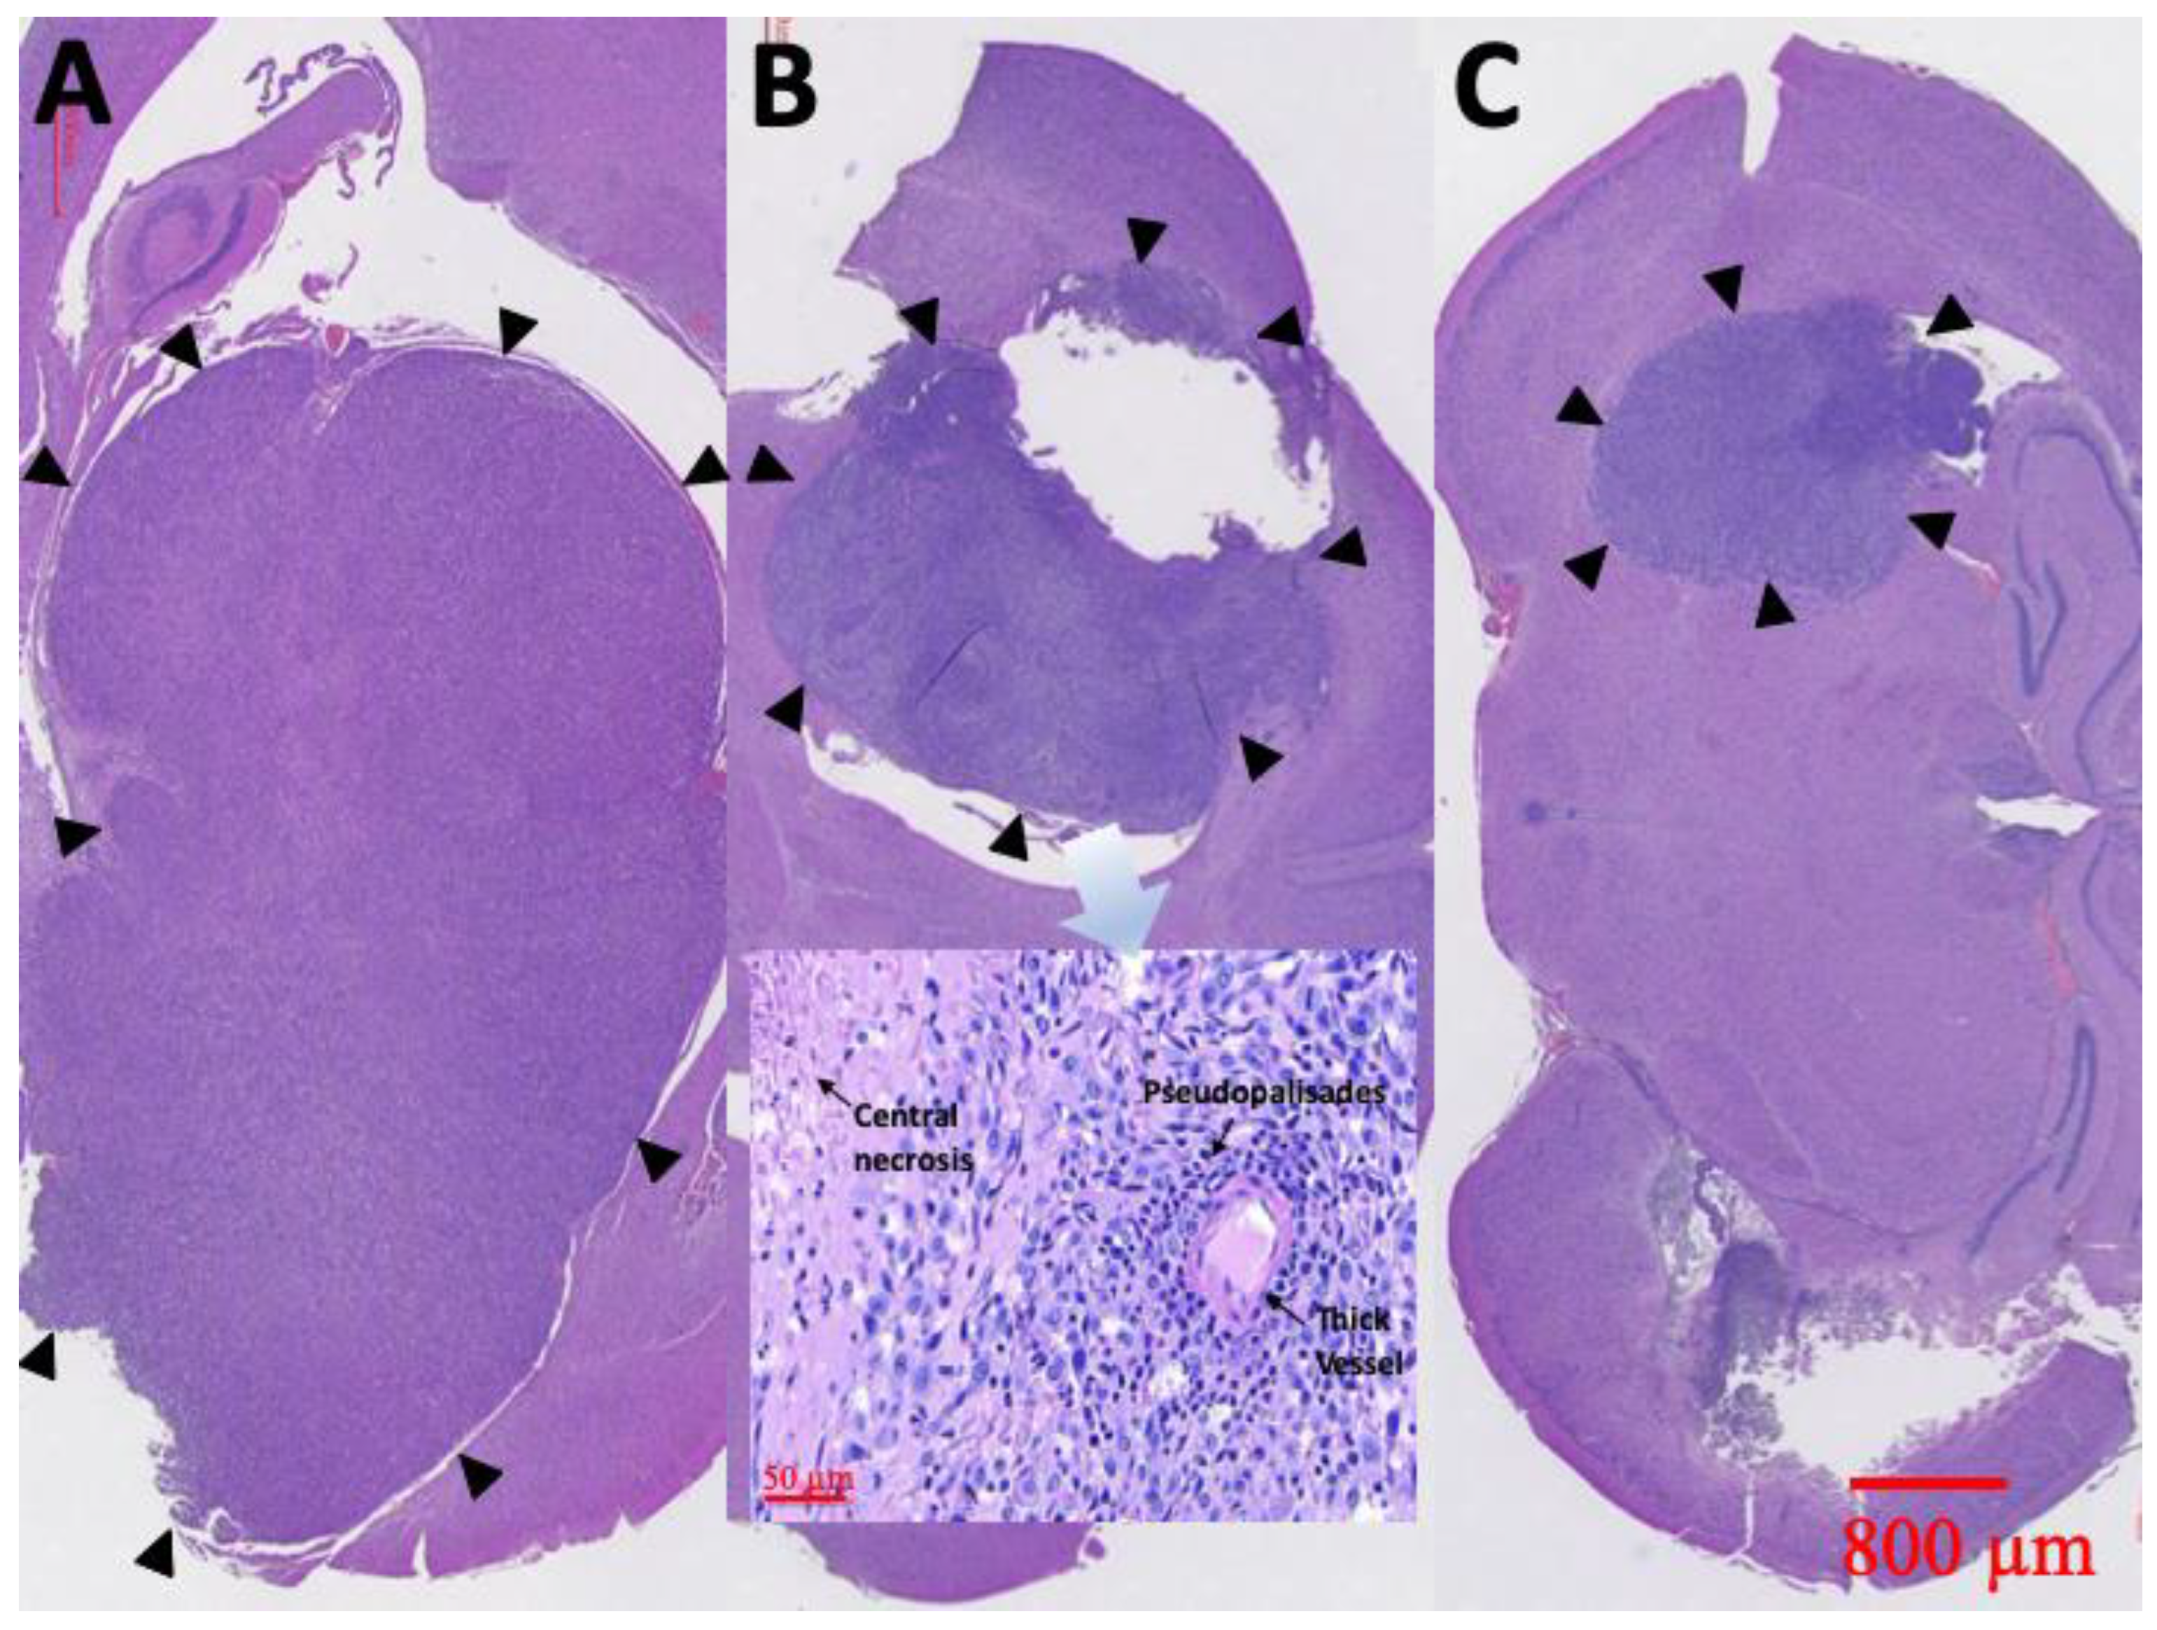

At least one rat in each group was sacrificed and the brain tissues meticulously extracted through surgery, 6 weeks after treatment. Figure 10 displays the results of the H&E staining. Group A rats had a large tumor region containing diffused karyorrhectic tumor cells, with either microvascular proliferation with thick vascular walls or coagulation necrosis. In addition, considerable serpiginous necrosis with palisading near the necrotic foci was noted. Group B rats had respectably multinucleated tumor cells with a localized area but with endothelial proliferation and less pseudopalisading necrosis. By comparison, the tumor area in group C rats was distinctly smaller and confined.

Figure 10.

H&E staining. Diffuse karyorrhectic tumor cells with central necrosis were observed in groups A and B. The tumor area and central necrosis were much greater in group A than in group B. Small tumor area and less central necrosis were observed in group C (the tumor edges are indicated by black triangles).